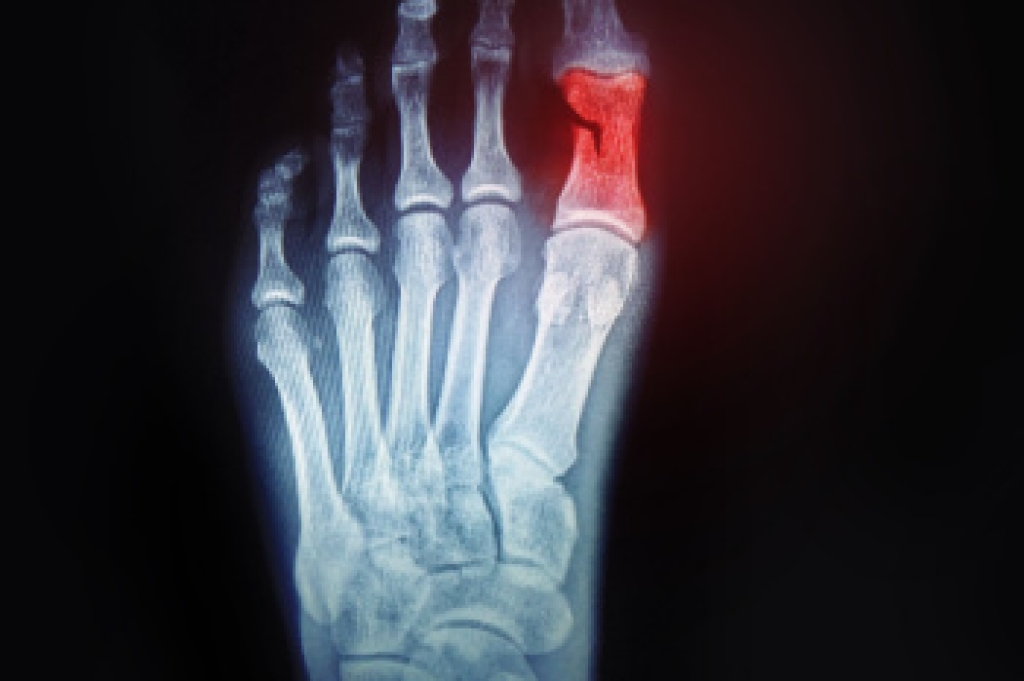

When people age, some common issues that may occur are bone density loss, dry skin, poor circulation, and rough brittle nails. These issues may also affect your foot health if the necessary steps are not taken to alleviate the problems.